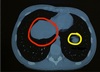

Define la patología o estructura estructura que encuentras en rojo y amarillo

Rojo: segmento hepatico 8vo Amarillo: efecto de volumen parcial